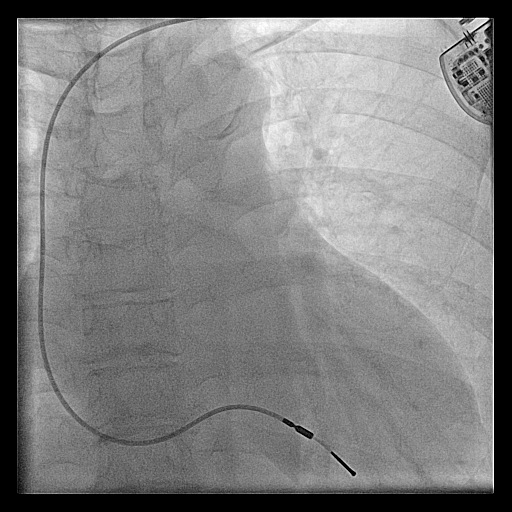

rvot_before_screw.jpg

RVOT pacing